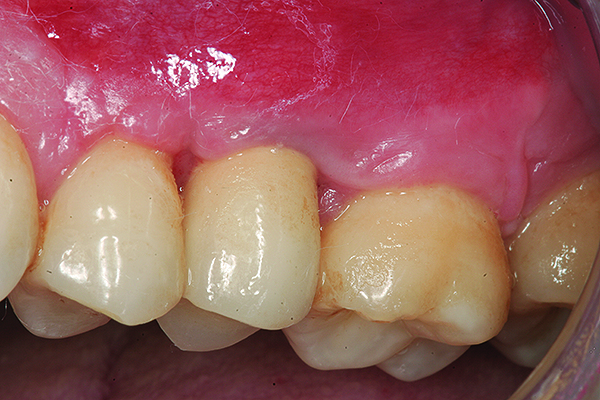

The implant restoration and surrounding soft tissue seen in Fig 3, 5 years following treatment.

Figure 4

Maxillary right lateral incisor implant restoration with severe bone and soft tissue loss is classified a major complication which may not be completely reversible.

Figure 5

A implant restoration with a buccal dehiscence of bone and soft tissue caused by poor implant positioning, lack of keratinized tissue prior to implant placement, and soft tissue recession post implant restoration.

Figure 8